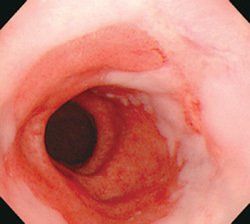

您現(xiàn)在所在位置:主頁 > 一科一特色 > 消化內(nèi)科 > 食管疾病 > Barrett食管 >

Barrett食管預(yù)防